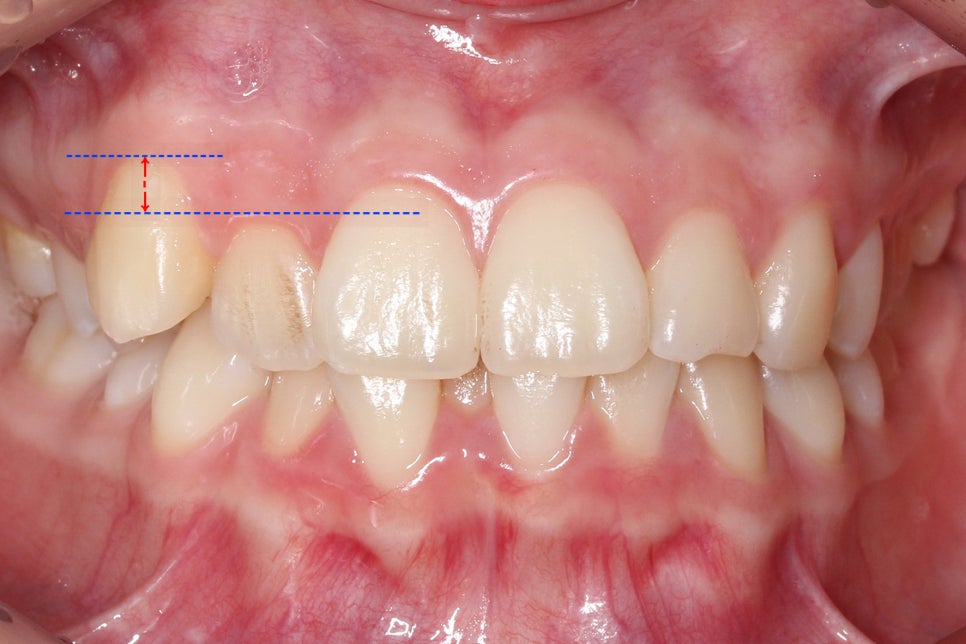

송곳니덧니 교정 Case로 구내사진을 보시면

사진 상으로 좌측 송곳니가 위쪽으로

변위되어 있는 모습을 확인할 수 있습니다.

이러한 경우 쉽게 증상을 알아 보려면

치아가 맹출된 높이를 확인하는 것이 좋은데요,

사진처럼 송곳니가 맹출된 높이가

주변 치열보다 월등히 솟아 있는 경우

high canine라고 할 수 있으며

송곳니덧니 교정 전 교합평면을 보면

송곳니의 높이가 다른 치아들보다

월등히 높은 곳에 위치한 것을 확인할 수 있는데요,

반대쪽 치열과 비교해보면 확연하게

그 차이를 알 수 있습니다.